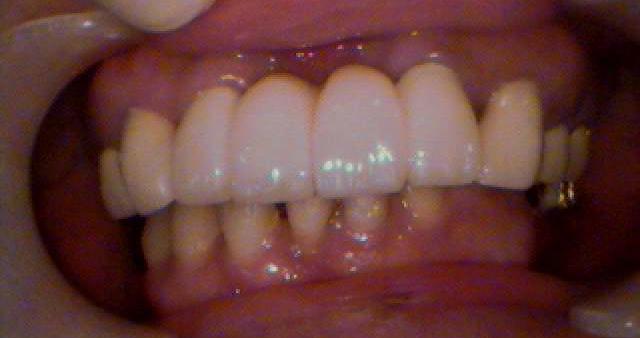

◆ インプラントにより、しっかりと噛めて食事を楽しめます!

審美的治療は、虫歯や歯周病など機能的に治療することに比べて、機能性に加え見た目の美しさも重視した治療方法です。

欠けてしまった歯並びや歯の色などを修復する際に、回りの歯の色と合わせて審美性(見た目)を回復させたり、黄ばんでしまった歯や歯ぐきを従来のような健康的な色に回復させるなどの治療を行うことで、自然に近い美しい口元にすることが可能です。

当院では、白く透明感があり、天然歯のようで目立たないながら、金属やセラミック以上の強度のある「ジルコニア」や、比較的低コストながら、長く使えるセラミックと歯科用プラスチックを合わせた「ハイブリッド」なども提供しております。